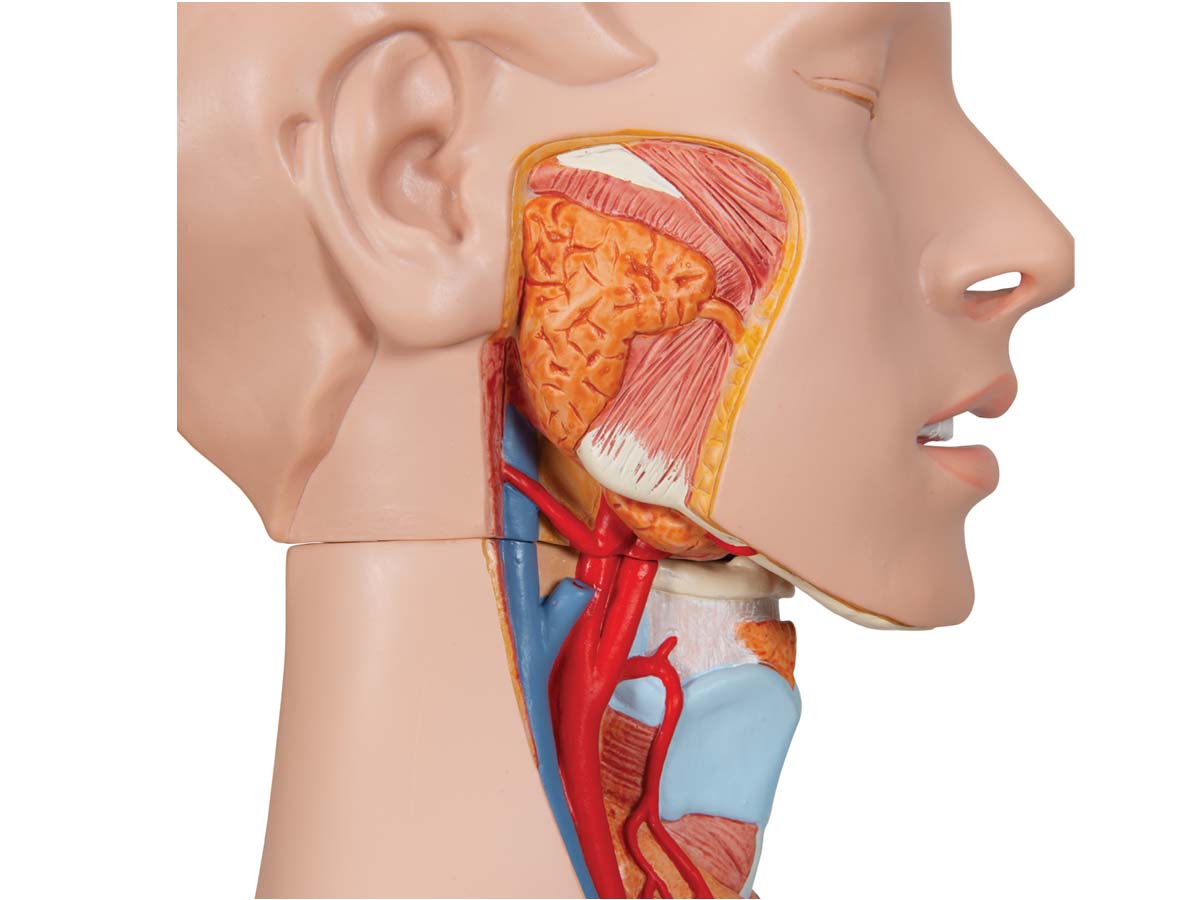

Der 3B Scientific Luxus-Torso bietet Ihnen alle Möglichkeiten für ausführliche Demonstrationen. Sie erhalten hunterprozentige Qualität und einen hohen Grad an Detailarbeit. Die Beschaffenheit der erweiterten Torso-Version ist beeindruckend, genau wie sein Preis! Beantworten Sie mit seiner Hilfe alle Fragen zur inneren Anatomie des Menschen. Er ist zerlegbar in:

– 3-teiligem Kopf